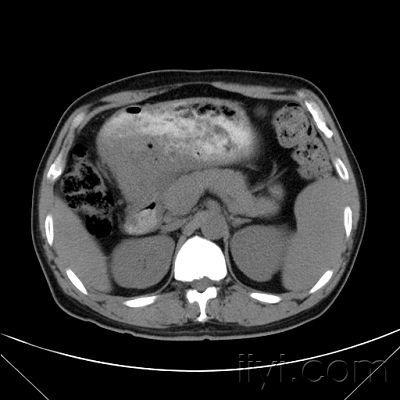

患者,女性,70岁,因"上腹胀,胃纳差,嗳气半月余"入院.

图片尺寸1843x1382